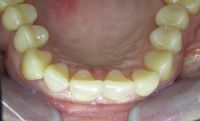

Voor de behandeling

De wens om de diastemen (de spleetjes) tussen de tanden gesloten te hebben.

Na de behandeling

Met composiet zijn de diastemen gesloten.